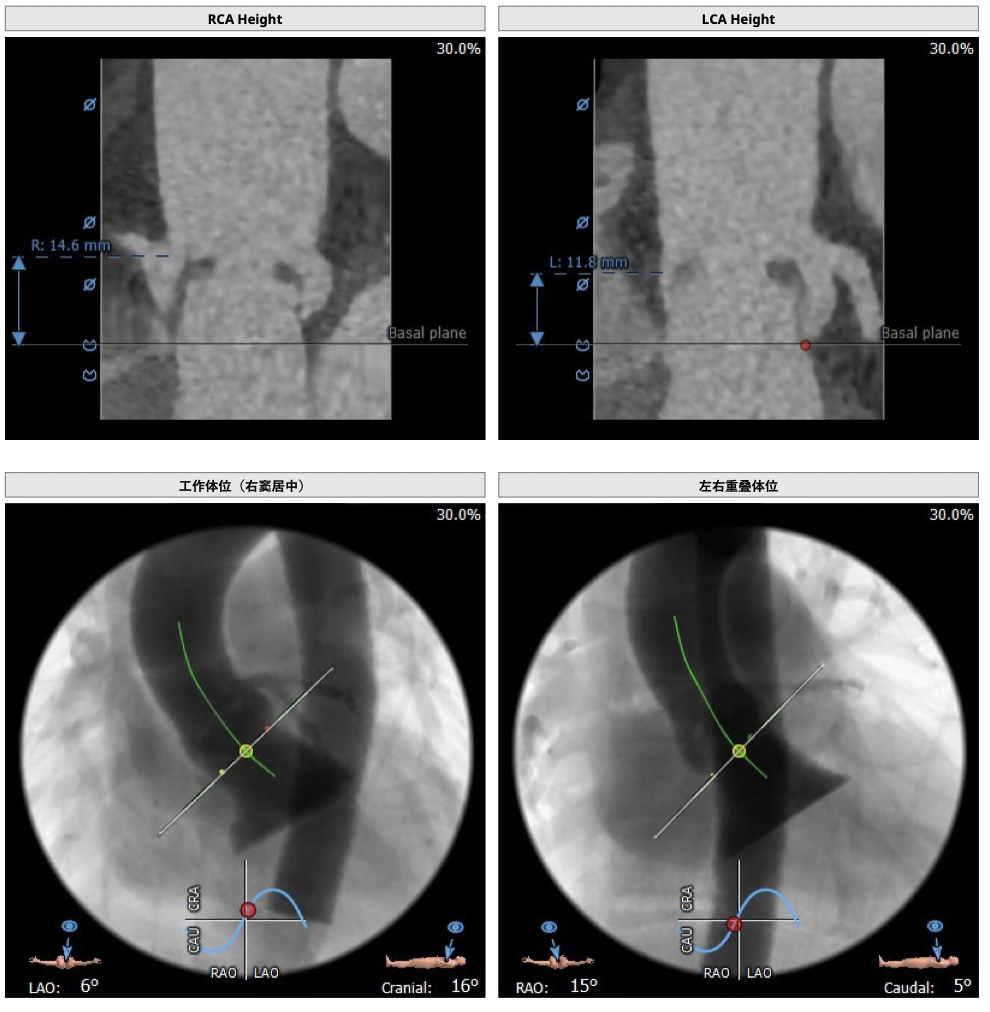

①患者因规律透析导致钙磷代谢紊乱,外周血管斑块钙化严重,最狭窄处仅2.8mm,通路建立难度极大(左右颈动脉均不符合入路条件);

③左冠高度不高,且瓣叶冗长,达冠脉开口层面,且冠脉存在狭窄,存在冠脉阻塞的风险;

确保冠脉安全,拟采取PCI+TAVR一站式手术策略,因患者右侧股动脉钙化严重、入路狭窄,拟采取无鞘法从右股动脉穿刺入路,选用20mm球囊预扩、L23号VenusA-Valve瓣膜、采用VenusA-Plus输送系统确保瓣膜的精确释放,瓣膜释放后结合造影和超声情况,决定是否后扩。